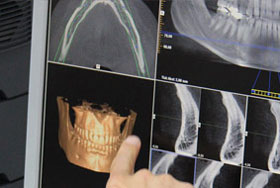

In der heutigen Zeit stellt gerade die Implantologie eine hervorragende Alternative zur prothetischen Versorgung mittels Brücken, Kronen und Prothesen dar. So ist die Oralchirurgie in Berlin ein wahrer Stützpfeiler für eine langanhaltende und dauerhafte implantierte Zahnkonstruktion. Ein Therapieerfolg der eine 98% Erfolgsquote aufweist. Zudem kann auf die festsitzende Konstruktion ein neuer Aufbau stattfinden. Oftmals verhindert dieses Verfahren in Schöneberg einen herausnehmbaren Zahnersatz. Eine geeignete Versorgungsform, die viele individuelle Patientenwünsche erfüllen kann. Mittels einer digitalen Volumentomografie kann in einer 3D Darstellung die Knochenqualität im Kiefer ermittelt und eruiert werden. In der Oralchirurgie in Lichtenrade entsteht somit eine Darstellungsqualität der knöchernen Strukturen. Nur so kann eine präoperative Planung der Implantate erfolgen. Die Implantationsoperation selbst ist meist ein schmerzloser Eingriff, der unter einer Lokalanästhesie vollzogen wird. So entsteht mit Eigenknochen, Knochenersatzmaterial und Knochentransplantationen ein langanhaltender Zahnersatz. Ein Therapieplan, der die Maßstäbe der Zukunft voll und ganz in der Oralchirurgie in Lichtenrade mit einbezieht.

Verschiedenste Ursachen, wie ein Unfall, Parodontitis oder Karies, können zum Zahnverlust führen. Dieser hat nicht nur ästhetische Auswirkungen, unter welchen die Betroffenen leiden, sondern kann auch das Kauverhalten und das Sprechen negativ beeinflussen. Eine der Kernkompetenzen der Oralchirurgie in Berlin stellt die Implantologie dar. Implantate ermöglichen nach Zahnverlust eine wahre Wiederherstellungsfunktion. Sie fungieren als künstliche Zahnwurzeln, welche nach dem Einsetzen und Einheilen die Vorbereitung für einen prothetischen Aufbau darstellen. Die Oralchirurgie in Berlin bedient sich hierbei Implantaten aus Titan. Dieses Material zeigt als Implantat ähnliche biochemische Eigenschaften wie die natürliche Zahnwurzel, wodurch es die Knochenbildung auf natürliche Weise anregt und so den gefürchteten Knochenschwund vermeidet. Die Implantologie zeigt sich dabei sehr vielseitig. Sie ermöglicht es nicht nur, einzelne Zähne zu ersetzen, sondern bietet auch andauernden Halt beim Verlust von mehreren oder sogar allen Zähnen. Mit Hilfe eines Digitalen High-Tech Volumentomographen (DVT) kann in der Oralchirurgie in Berlin die Knochenqualität überprüft und dargestellt werden. Diese Methode ermöglicht die Planung der Implantate auf 3D-Ebene und so die Erstellung einer genauen Implantationsschablone. Das Implantat wird dann in den Knochen eingebracht, durch ein Provisorium verschlossen und heilt innerhalb weniger Monate in den Kieferknochen ein. Auf aufgeschraubte Implantatpfeiler - die Träger sozusagen - werden die Kronen zementiert oder verschraubt. So dienen sie als andauernder Anker für verschiedenste Prothesen. Die Entscheidung für die Implantologie als Teilbereich der Oralchirurgie in Berlin verhindert zudem, dass gesunde Zähne beschliffen werden müssen, wenn diese als Anker für z. B. Brücken dienen sollen. Implantate bleiben dauerhaft im Knochen und ermöglichen über viele Jahre, wenn nicht sogar ein Leben lang, einen stabilen Ersatz für verloren gegangene Zähne.